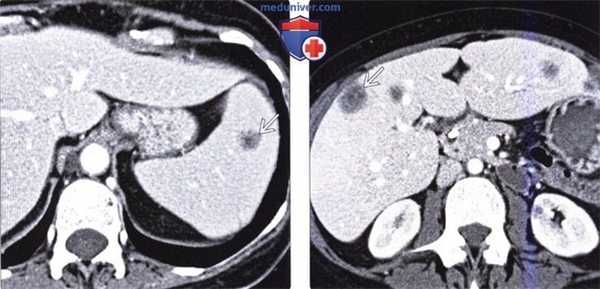

(Справа) На аксиальной КТ с контрастом визуализируется гидатидная киста селезенки, а также другие похожие очаги в печени и брюшной полости, большинство из которых содержит кальцинаты в стенке. У этого пациента ранее имел место разрыв гидатидной кисты печени, что привело к распространению инфекции по всей брюшной полости.

(Слева) На аксиальной КТ с контрастным усилением у наркозависимого пациента 29 лет (вводящего наркотики внутривенно) с жалобами на лихорадку и боль вверху живота слева в течение трех дней, определяется гиподенсный очаг в периферических отделах средней части селезенки (абсцесс).

(Справа) На аксиальной КТ с контрастным усилением у этого же пациента определяются воспалительные изменения около селезенки, которые можно трактовать как разрыв абсцесса. При эхокардиографии были обнаружены многочисленные вегетации на аортальном и митральном клапане, наличие которых позволяет предположить, что абсцесс возник в результате эндокардита.